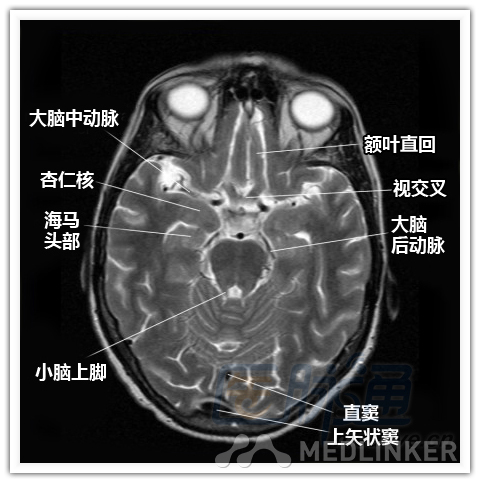

简明易懂的脑部断层解剖:横断位MRI(1)

本文将对不同横断位的脑部MRI图像进行标示,主要讲解内容是脑部基本解剖。脑部横断位解剖,尤其是内囊层面的影像学解剖一直是一大重点,一起来学习一下。 横断位图像顺序:由足侧至头侧 本文转载自医脉通。 声明:本文转载是出于提供更多信息以参考使用或学习、交流之目的,不用于商业用途。转载无意侵犯版权,如转载文章涉及您的权益等问题,请作者速来告知,我们将尽快做删除处理。